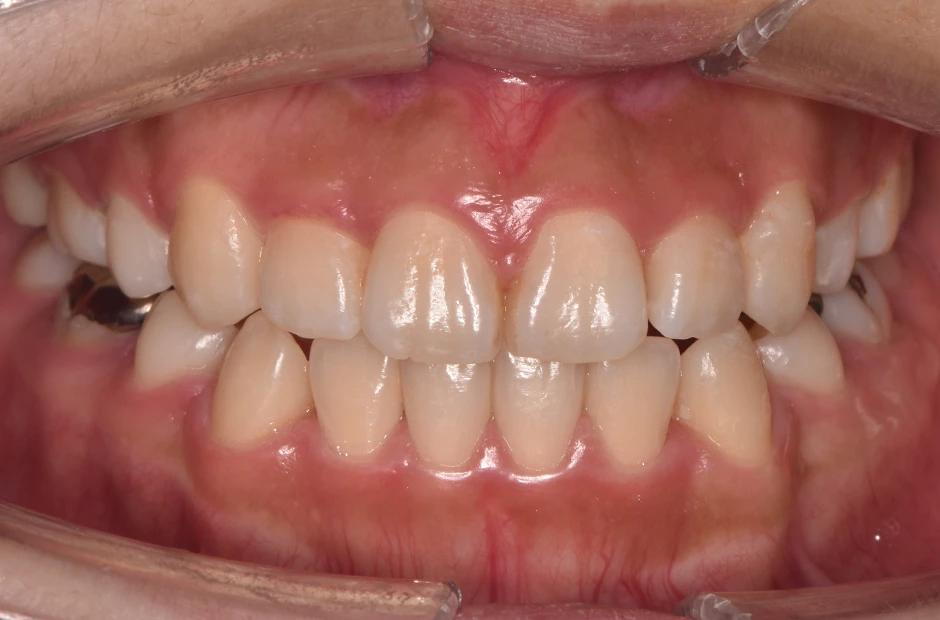

治療症例

ブラケット矯正

前歯部反対咬合

| 診断名・主訴 | 前歯部反対咬合 |

|---|---|

| 年齢・性別 | 14歳・男性 |

| 治療期間・回数 | 1年2か月 |

| 治療に用いた主な装置 | ブラケット矯正 |

| 抜歯部位 | なし |

| 治療費 | 60万円(税抜) |

| リスク・副作用 | 装置による違和感・疼痛・歯肉退縮・歯根吸収・虫歯のリスクなど |

治療後